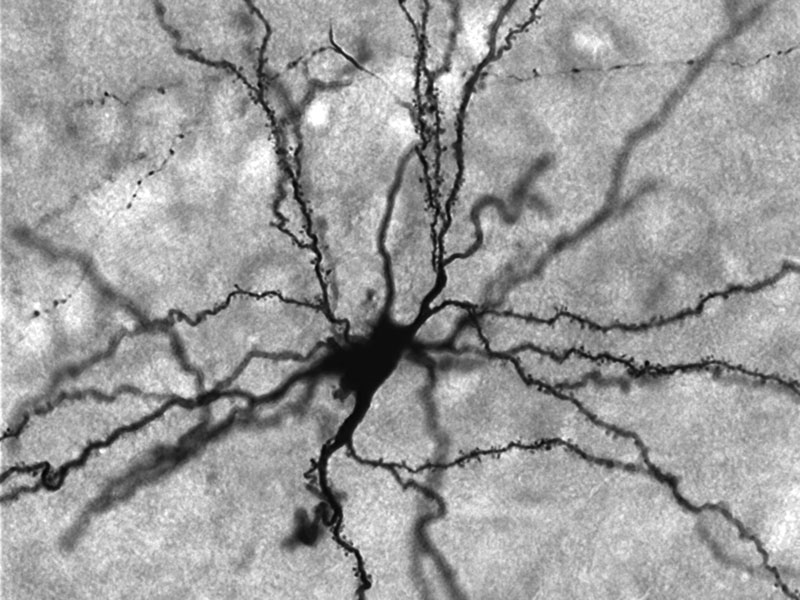

Gli scienziati hanno focalizzato la loro attenzione sui circuiti nervosi nell’amigdala, la parte del cervello responsabile del condizionamento alla paura sia sulle persone che sugli animali.

Incutendo paura ai topolini tramite l’uso del suono, gli scienziati hanno osservato che alcune cellule dell’amigdala hanno condotto piu’ corrente dopo che la cavia e’ stata esposta a un forte e improvviso suono. In questo modo i ricercatori hanno trovato aumenti temporanei nella quantita’ di particolari proteine entro un paio d’ore dal condizionamento alla paura che ha raggiunto un picco a 24 ore ed e’ scomparso 48 ore dopo.